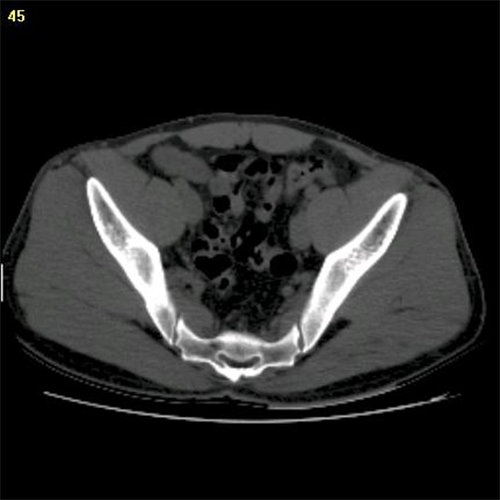

View X-Ray CT & MRI Scans Fast and Easily

FREE and easy to use 3D DICOM Viewer – for surgeons and patient education

Traditional multi-planar slicing

Designed mainly for CT and MR DICOM modalities.

Multi-planar slicing.